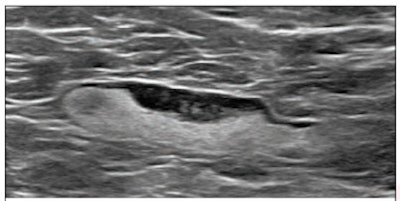

(Above) 55-year-old woman who underwent screening mammogram and ultrasound seven days after first COVID-19 vaccination dose. Screening mammogram and US demonstrated unilateral left axillary lymph node with cortical thickness of 5 mm on ultrasound (not shown). BI-RADS category 0 was assigned. Ultrasound from diagnostic work-up performed seven days later showed no change in lymph node size. BI-RADS 3 was assigned. (Below) 41-year-old woman who underwent high-risk screening breast MRI 15 days after first COVID-19 vaccination dose. Sagittal T1-weighted fat-saturated contrast-enhanced MRI shows extensive unilateral left level I-II axillary adenopathy. BI-RADS 3 was assigned. Images and captions courtesy of the American Roentgen Ray Society.

(Above) 55-year-old woman who underwent screening mammogram and ultrasound seven days after first COVID-19 vaccination dose. Screening mammogram and US demonstrated unilateral left axillary lymph node with cortical thickness of 5 mm on ultrasound (not shown). BI-RADS category 0 was assigned. Ultrasound from diagnostic work-up performed seven days later showed no change in lymph node size. BI-RADS 3 was assigned. (Below) 41-year-old woman who underwent high-risk screening breast MRI 15 days after first COVID-19 vaccination dose. Sagittal T1-weighted fat-saturated contrast-enhanced MRI shows extensive unilateral left level I-II axillary adenopathy. BI-RADS 3 was assigned. Images and captions courtesy of the American Roentgen Ray Society.